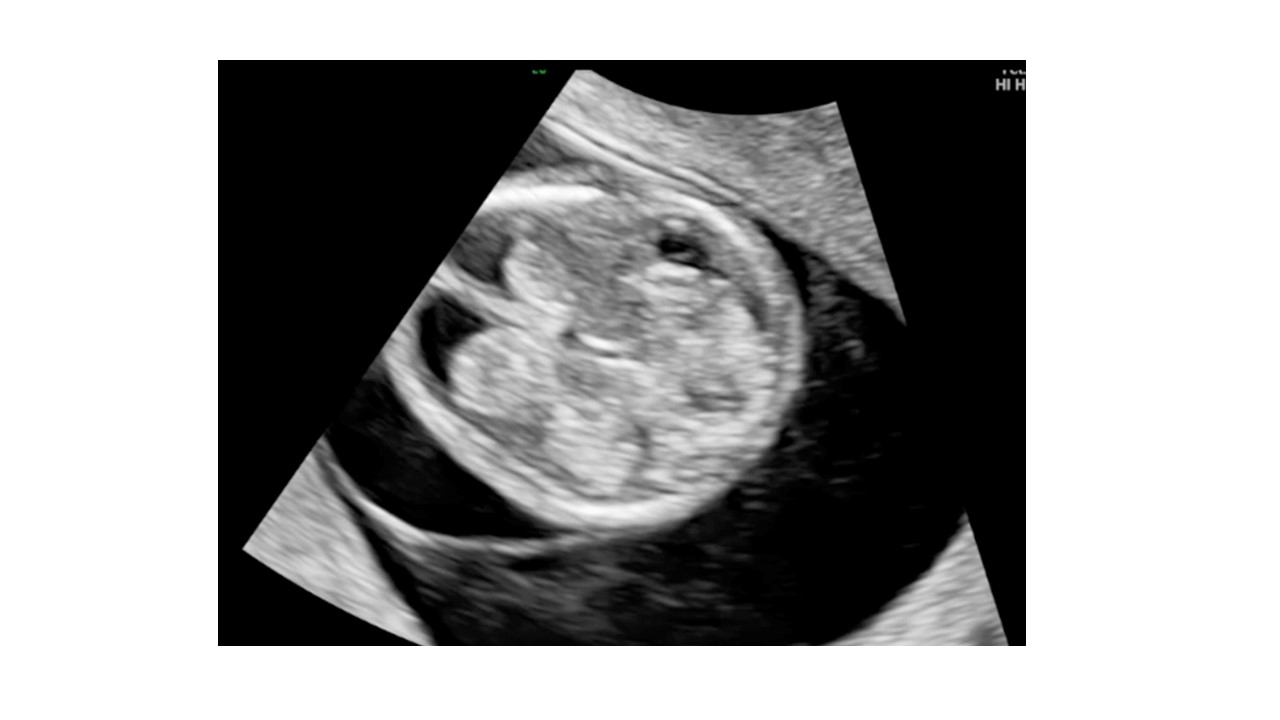

Siêu âm hình thai học quý I